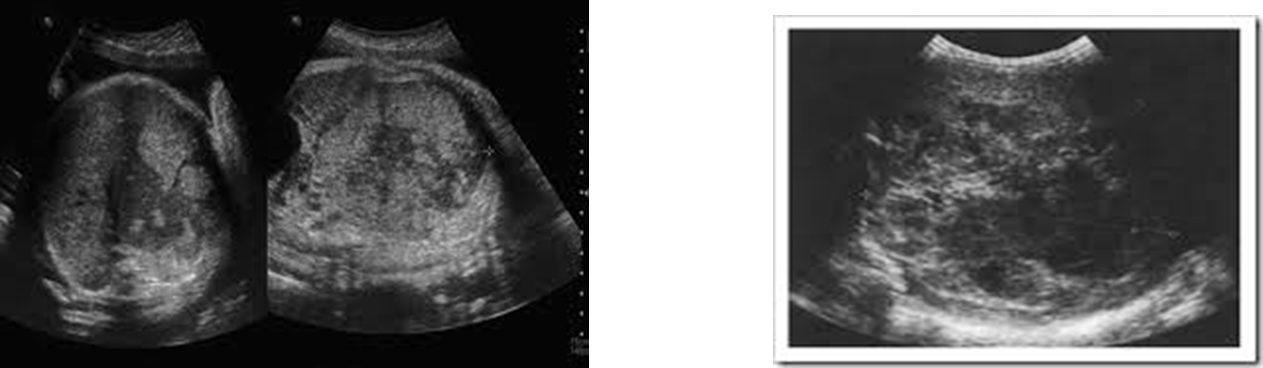

hepatoblastoma

malignant liver tumor found almost exclusively in infants and young children

most common hepatic malignancy in children

what is often associated with Beckwith-Wiedemann syndrome

clinical indication of hepatoblastoma

elevated alpha fetoprotein